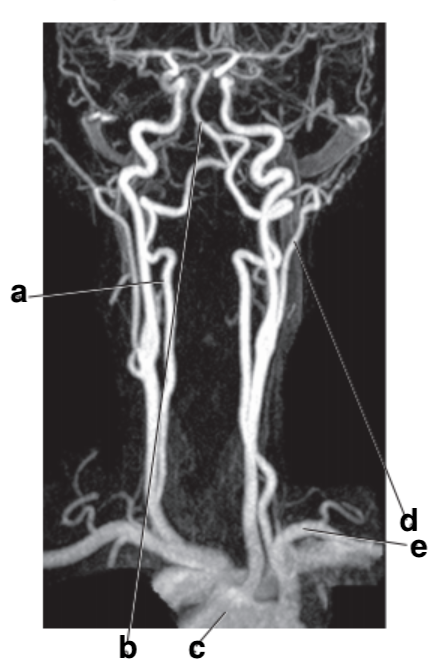

Which letter is the popliteal artery?

A

The femoral artery is an extension of which artery?

External iliac

What is letter d?

left popliteal artery

What is letter b?

Basilar artery